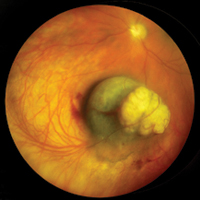

Ocular OncologyImage

Associate Professor and Director, Section of Ocular Oncology

Rush residents have the unique opportunity to evaluate and manage patients who have benign and malignant tumors of the eye and adnexa. The ocular oncology service is under the direction of Jack A. Cohen, MD, the only fellowship trained ocular oncologist in Chicago. Each year, approximately 20 patients are seen with a variety of eye tumors. Dr. Cohen emphasizes preoperative, operative and postoperative management of these patients with the residents. Residents are exposed to the evaluation and follow-up of these patients, including standardized ultrasonography, radiology, MRI and CT scanning, and biomicroscopy. Additionally, experience with various surgical procedures is obtained, including fine needle biopsy, vitreous and conjunctival biopsy, plaque brachytherapy, external beam teletherapy, dosimetry, spray cryotherapy, transpupillary thermotherapy, chemoreduction and cryotherapy. Surgical therapy of orbital and adnexal tumors are coordinated with the Cornea and External Disease, Oculoplastic, and Neuro-Ophthalmology Sections. At the completion of training, residents are proficient in the recognition, management and referral of patients with a variety of ocular tumors.